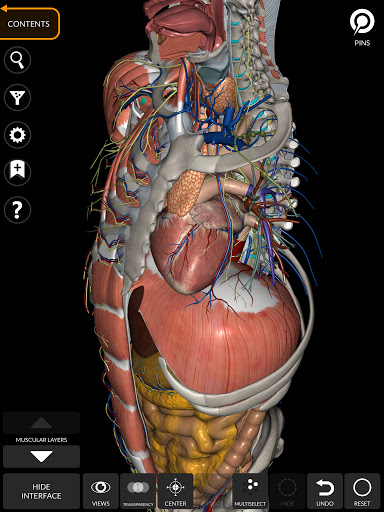

"Anatomía - Atlas 3D" permite estudiar la anatomía humana de forma fácil e interactiva.

A través de una interfaz sencilla e intuitiva es posible observar cada estructura anatómica desde cualquier ángulo.

Los modelos anatómicos 3D son especialmente detallados y con texturas de hasta una resolución de 4k.

La subdivisión por regiones y las vistas predefinidas facilitan la observación y el estudio de partes individuales o grupos de sistemas y las relaciones entre los diferentes órganos.

MODELOS ANATÓMICOS 3D

nervioso • Sistema respiratorio • Sistema digestivo • Sistema urogenital (masculino y femenino) • Sistema endocrino • Sistema linfático • Sistema ocular y auditivo CARACTERÍSTICAS • Interfaz sencilla e intuitiva • Rotar y hacer zoom en cada modelo en el espacio 3D • Opción para ocultar o aislar uno o varios modelos seleccionados • Filtro para ocultar o mostrar cada sistema • Función de búsqueda para encontrar fácilmente cada parte anatómica • Función de marcador para guardar vistas personalizadas • Rotación inteligente que mueve el centro de rotación automáticamente • Función de transparencia • Visualización de músculos a través de niveles de capas desde las superficiales hasta las más profundas • Al seleccionar un modelo o un pin, aparece el término anatómico relacionado • Descripción de los músculos: origen, inserción, inervación y acción • Mostrar/ocultar interfaz de usuario (muy útil con pantallas pequeñas) MULTILINGÜE • Los términos anatómicos y la interfaz de usuario están disponibles en 11 idiomas: latín, inglés, francés, alemán, italiano, portugués, turco, ruso, español, Chino, japonés y coreano • Los términos anatómicos se pueden mostrar en dos idiomas simultáneamente REQUISITOS DEL SISTEMA • Android 8.0 o posterior, dispositivos con al menos 3 GB de RAM Reversi